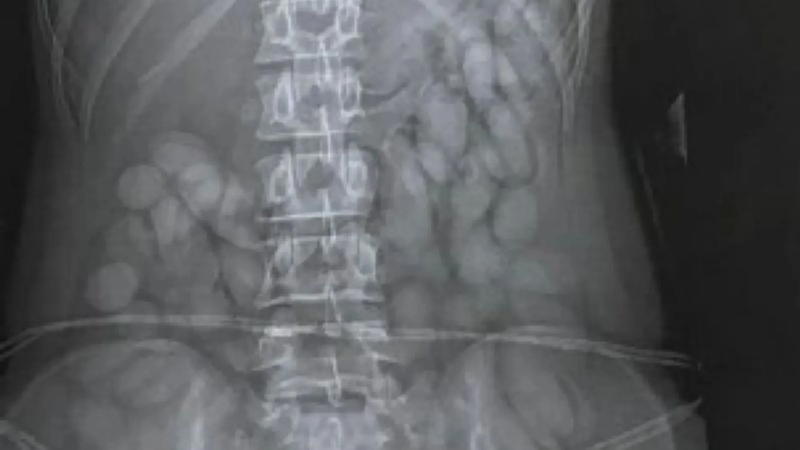

In the latest incident, a 43-year-old Paraguayan man was arrested after a medical examination confirmed he had swallowed multiple foreign objects, later identified as 20 bullets suspected to contain cocaine.

Just a week earlier, a 21-year-old woman was arrested after passing 110 bullets of cocaine. She too had arrived on a flight from São Paulo and was taken to a hospital where foreign objects were detected in her stomach.